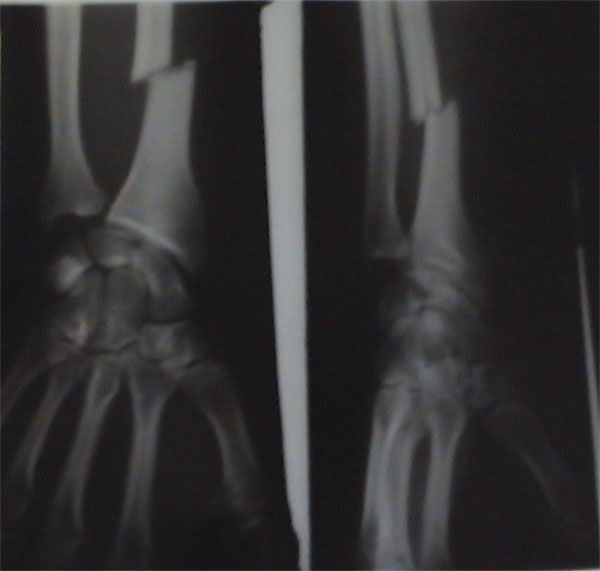

je tiens a remercier tout particulièrement les gens du Centre Hospitalier de Grenoble ki m’ont offert une magnifique plaque en fer et 6 vis pour mon bras ainsi qu’un superbe platre blanc !!

Ha ouai quand même Quand tu pète quelque chose, tu le fait bien

Bien réparé en tout cas Sont bon au centre hospitalier de grenoble

Ah ouais pas mal en effet, tu as du le sentir passer.